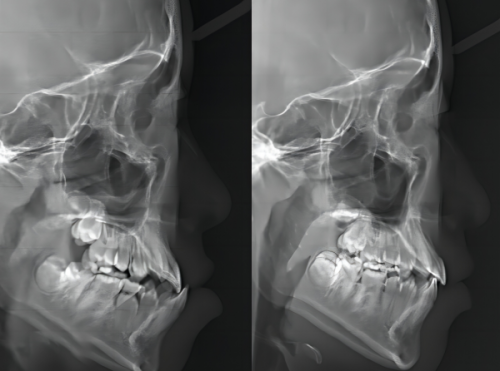

14. 牙齿矫正(金属托槽):5000 - 12000元

15. 牙齿矫正(隐形矫正):15000 - 30000元

4. 我想矫正牙齿,在这里询问后,医生根据我的牙齿情况制定了详细的矫正方案。矫正过程中,医生会定期检查我的牙齿情况并调整方案。现在我的牙齿已经整齐了特别多,成效非常明显。医生和护士都特别亲切,让我在矫正过程中没有感到任何压力,我真的特别推荐这里。